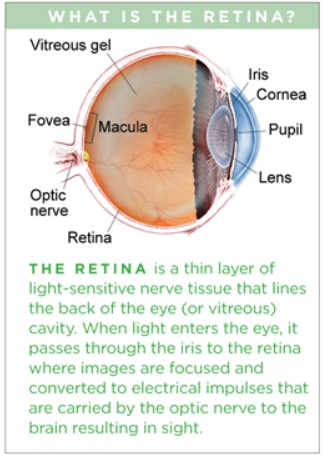

Your Eyes and Detachments

Vitreous Humor: This is a gel-like substance that fills the eye, primarily composed of water and collagen. At birth, it has a gel state due to a network of fine collagen fibrils. With age, the collagen fibrils aggregate and the vitreous becomes more liquid, leading to a condition known as vitreous liquefaction. This process typically begins around age four and continues throughout life.

Vitreous Detachment: As the vitreous shrinks and liquefies, it may pull away from the retina, a phenomenon referred to as posterior vitreous detachment (PVD). This usually occurs after age 50, with increased risk as one ages. During PVD, the vitreous can exert tearing pressure on the retina due to its attachment at certain points. This can lead to complications such as retinal tears or detachment.

Symptoms: Common symptoms of vitreous detachment include an increase in floaters (small dark spots in vision) and flashes of light in your peripheral vision. These occur when strands of the vitreous cast shadows on the retina and/or tug on it. You need to get them checked, but chances are you are OK. The things to be really focused on are symptoms of retinal detachment. They include bright flashes of light, especially in peripheral vision, blurred vision, new floaters in the eye that appear suddenly, and/or what happened in my case, shadowing or decreased peripheral vision that seems like a curtain or shade across your vision. The latter is a big deal – don’t let anyone try to convince you that it’s “just a big floater” which is what happened to me.